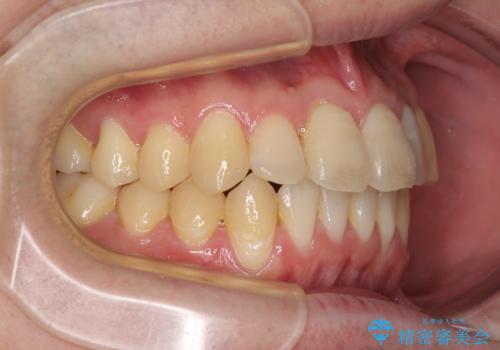

前歯のクロスバイト インビザラインによる矯正治療

- 上下のクロスバイトと前歯のデコボコを気にして来院された患者様です。

インビザラインを用い、IPR(歯と歯の間を削る)と歯列全体を拡大させることで、歯並びを整えていくこととしました。

上下ともに歯列全体を後方に移動させるため、上下の親知らずを抜歯することとしました。

奥に位置していた上の前歯が下の前歯を乗り越える際、奥歯でものを咬むことができず、辛い時期が続きました。